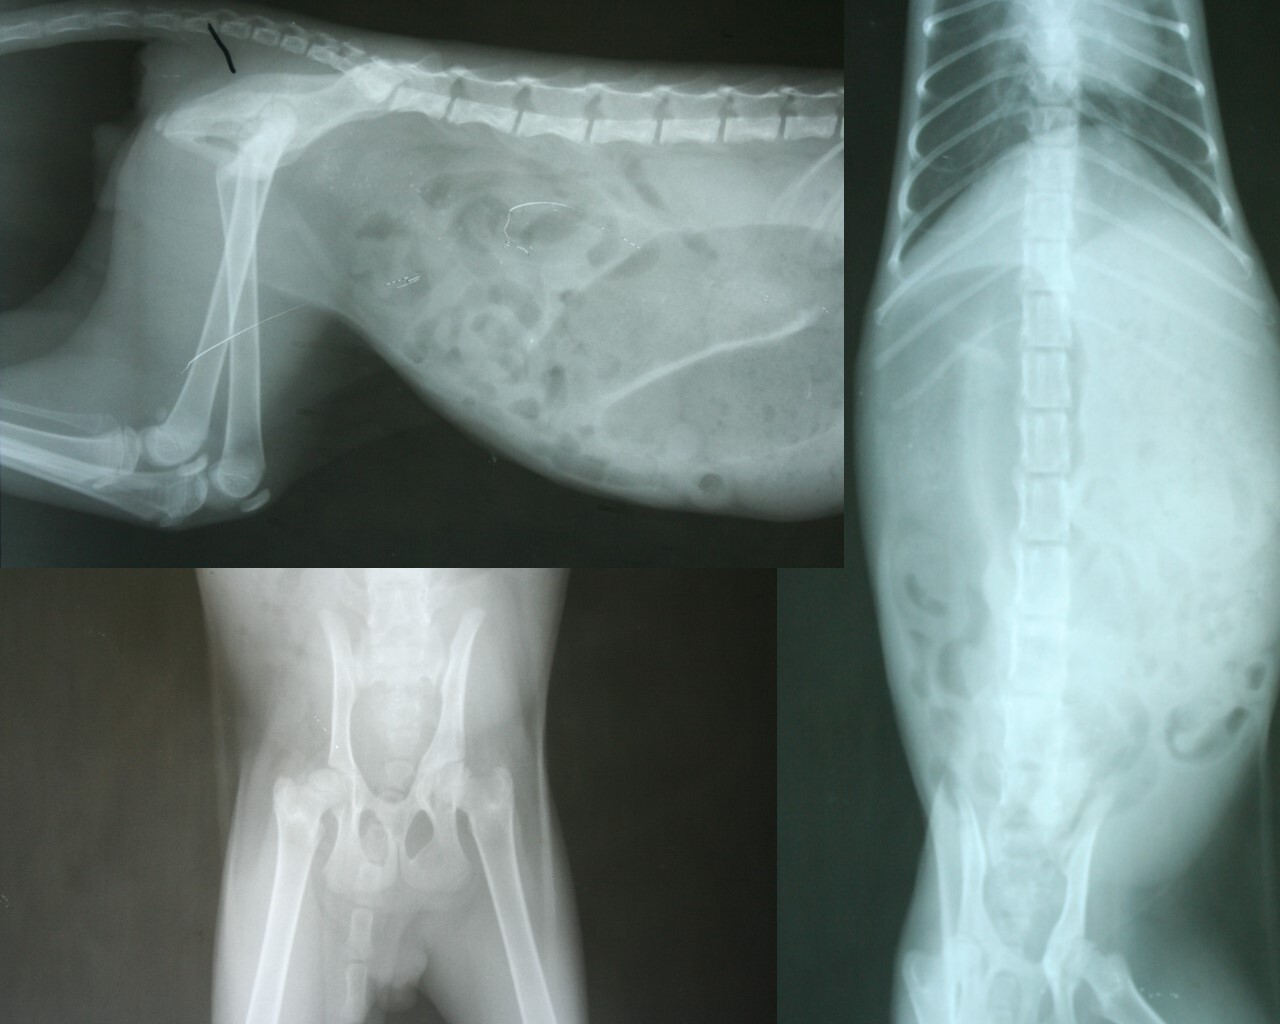

X光片顯示之前應該有遭遇車禍或由高處墜下

左惻骨盆腸骨至大轉節處有斷裂過

所以先以麻醉灌腸排出所有大便

(文中觀察照片為第2.3.6.7天的排便狀況)